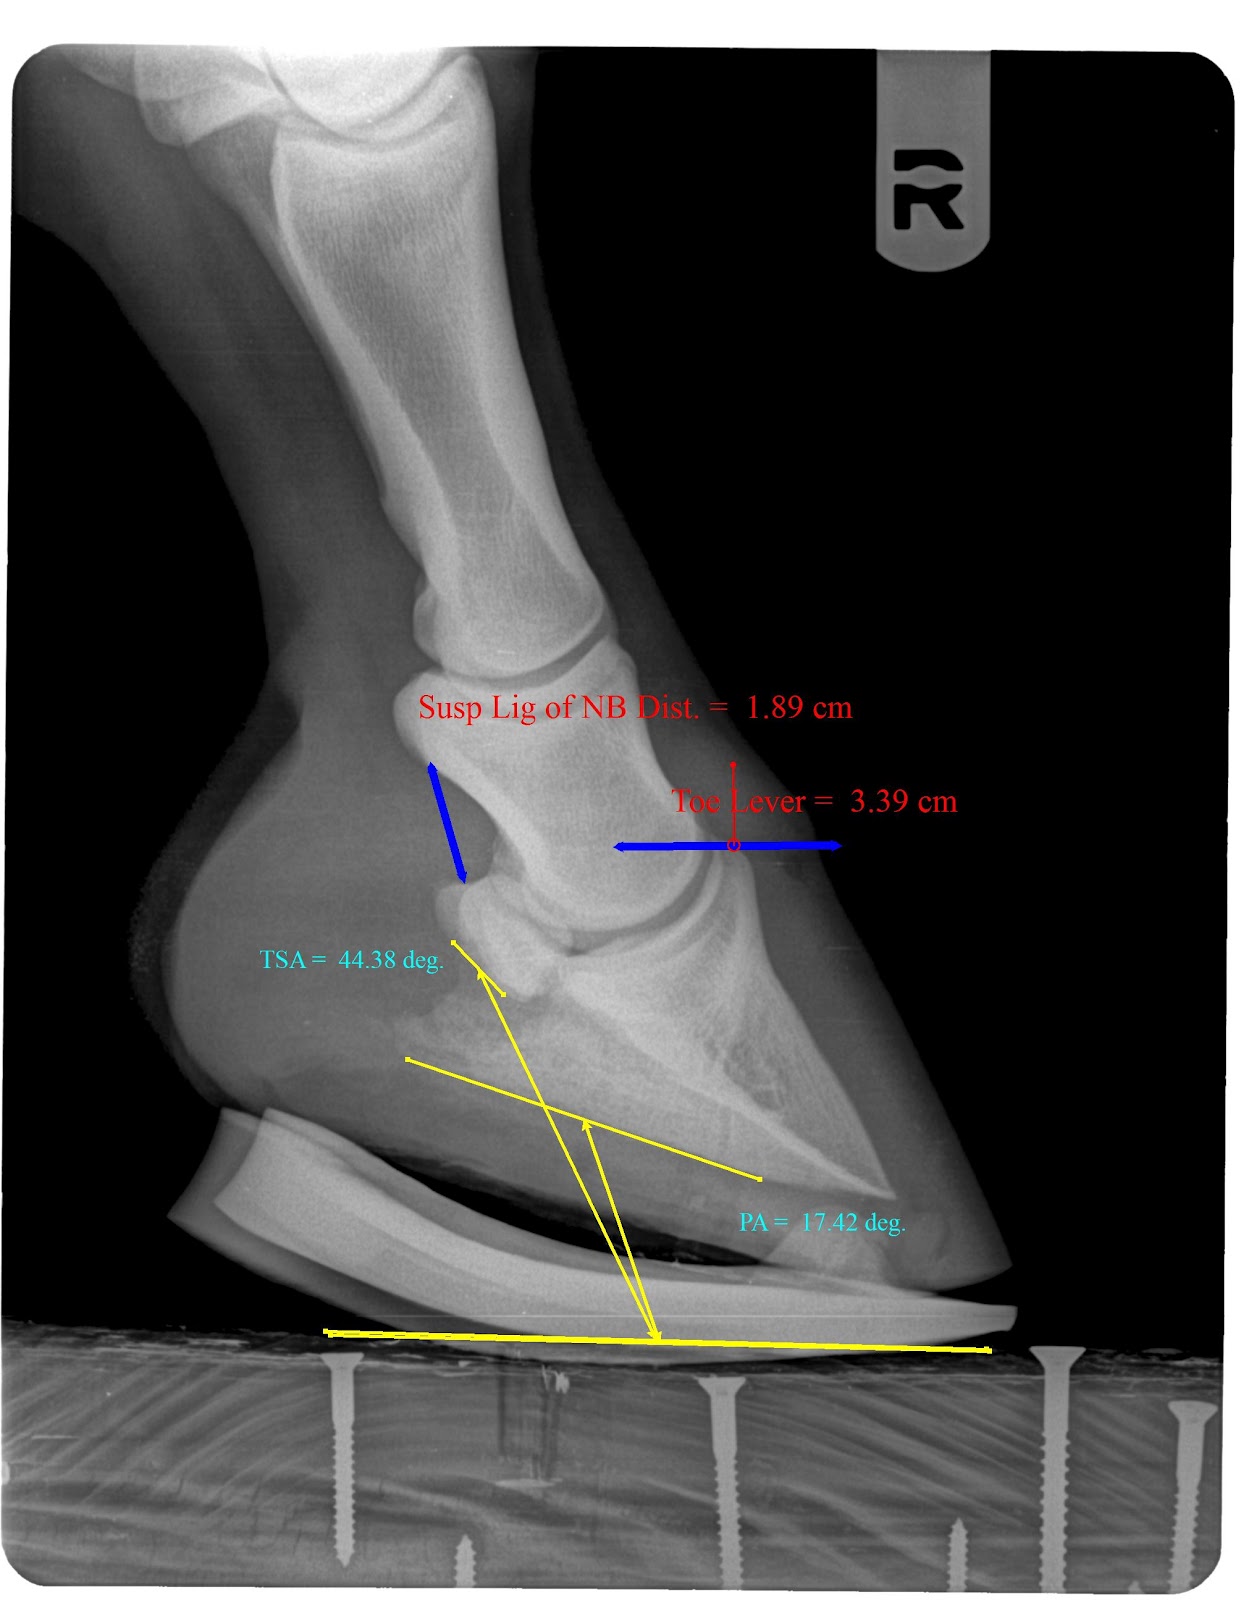

| Pre shoe farrier friendly radiograph |

| Post shoe radiograph |

Note the better digital alignment the drastic change in palmar angle, tendon surface angle and reduced toe lever. This shoe changed PA by 12-14 degrees which will unload the tendons load on the navicular bone by 50 to 60 percent.